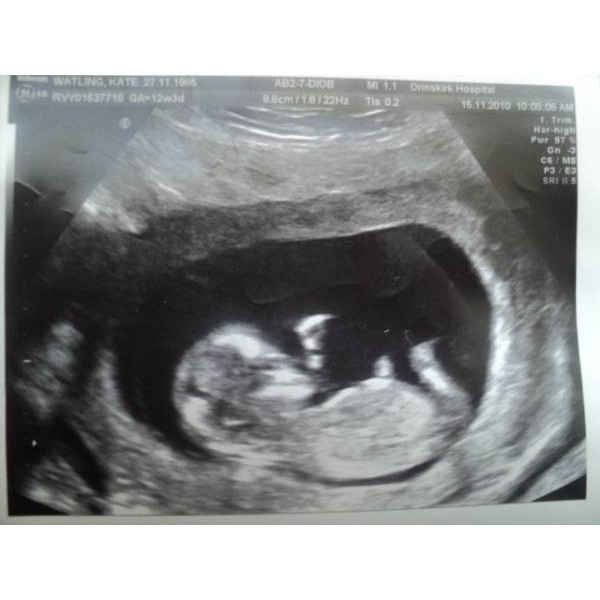

День узи я счастлива, но всё ещё чего то боюсь...

-Всё в норме, ручки , ножки уже есть развитие идёт хорошо, по размерам соответствует 12нелель 2дня💞

12недель счастья

Выхожу из кабинета окрылённая, присылаю фото мужу, он звонит счастливый,